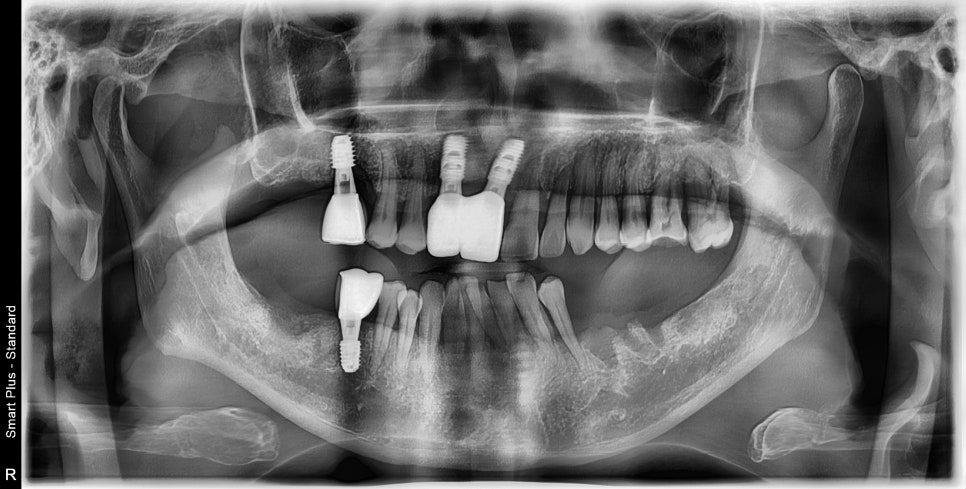

전반적으로 스케일링과 치주치료를 진행한 후 사진입니다.

이미 내려앉은 잇몸은 다시 채울 순 없지만 더 이상의 염증의 진행을 막고

부어있던 잇몸을 가라앉혀야 임플란트나 다른 치료들이 예후성이 좋아집니다.

일반적으로 치주가 안 좋은 환자분들은 치아 개수에 맞춰 어금니의 개수를

모두 회복할 수 있는 임플란트 수술을 권장하지만

이번 케이스는 주어진 상황상 맨 끝 어금니는 수복하지 못했습니다.

임플란트가 완성될 시기쯤 흔들림이 심해진 좌측 아래 어금니는

발치가 불가피했습니다.

오른쪽 교합이 어느 정도 완성이 됐기 때문에 그 주변 치아는

흔들림이 줄어들 것이며 반대편의 교합도 완성시키기 위해서는

앞선 치료와 같은 방식으로 치료가 진행되어야 합니다.